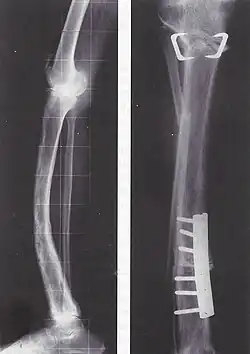

Im weiteren Verlauf geht die Entzündung zurück und hinterlässt eine dichte, aber unregelmäßige Sklerosierung (kalkreiche Verdichtung) des Knochens, oft auch Deformierungen, druckbedingte Verbiegungen und Auftreibungen der befallenen Skelettelemente, wie eine Wirbelsäulenverkrümmung, einen gewölbter Brustkorb und eine Krümmung der Beine. Bei einer Verdickung der Knochen der Lendenwirbelsäule können Ischiasschmerzen auftreten, die bis ins Bein ausstrahlen (Wurzelkompressionssyndrom).

Die Behandlung ist symptomatisch mit schmerzlindernden und entzündungshemmenden Medikamenten wie Nichtsteroidalen Antirheumatika, Entlastung des Knochens, Krankengymnastik und gegebenenfalls operativer Stabilisierung von Knochenbrüchen. Tritt keine Besserung der Symptome ein, können Medikamente den Verlust der Knochenmasse verhindern und Schmerzen lindern; Bisphosphonate und Calcitonin hemmen den Knochenabbau und können bei rechtzeitiger, regelmäßiger Einnahme Deformierungen verhindern. Neuerdings stehen auch Bisphosphonate (Zoledronat, Aclasta®; Pamidronat, Aredia®) zur intravenösen Infusion zur Verfügung. Sie ersetzen die tägliche Tabletteneinnahme. Die einmalige Infusion von Zoledronat hat eine Wirkungsdauer von über einem Jahr. Ergänzend werden Vitamin D und Calcium verschrieben. Bei einer besonders schweren Schädigung der Hüfte kann ein Hüftgelenkersatz erforderlich sein.